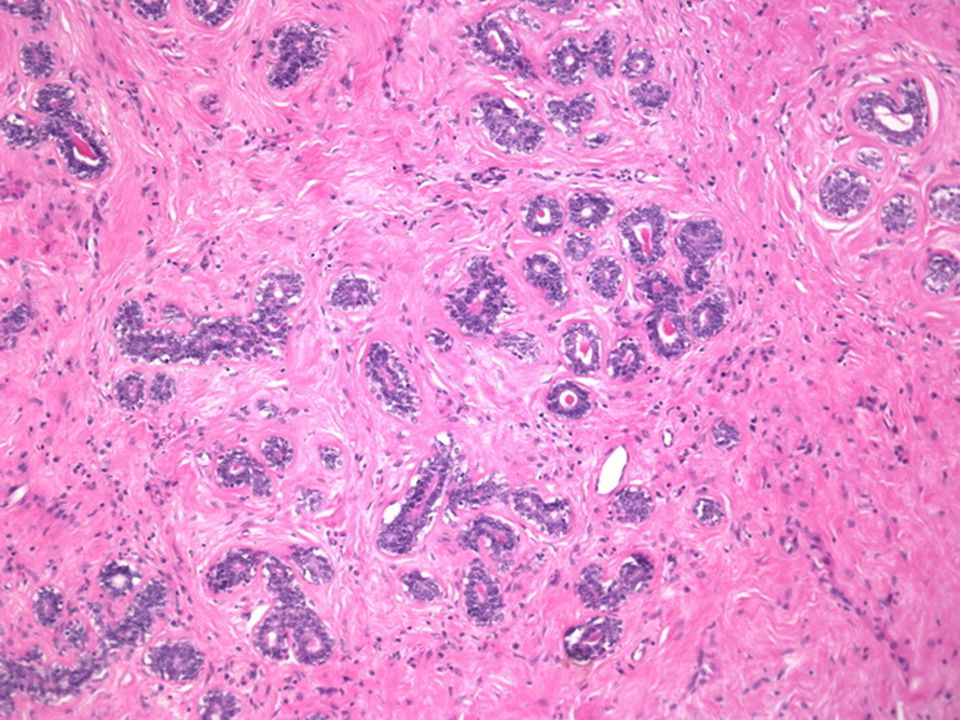

Раздел: Снимки-откровения